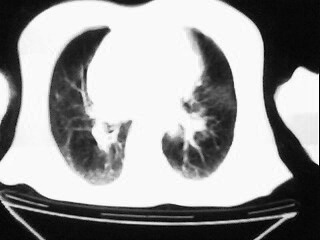

女,79,咳 嗽月余,无其它不适

1)两肺炎症。2)食管裂孔疝可能;建议行上消化道钡餐检查。

后纵隔内左心房至肝左叶后方椎体中线偏左巨大软组织包块,其壁均匀比较薄,其内可见宽气液平。

考虑食管裂孔疝。建议钡餐检查